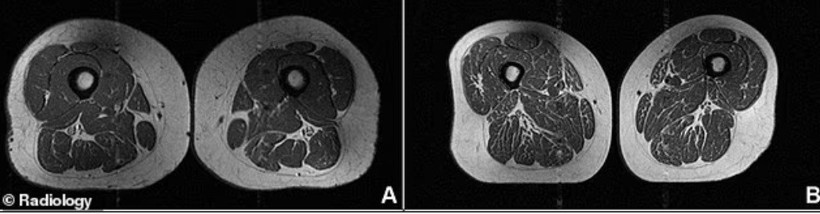

Bilim insanlarının yayımladığı bir çalışmada, aşırı işlenmiş gıdalarla beslenen bireylerin kaslarında “mermerleşme” olarak tanımlanan bir durum tespit edildi. Bu durum, kas liflerinin arasına ve içine yağ birikmesi anlamına geliyor.

Araştırmada incelenen bir vakada, beslenmesinin yüzde 87’si işlenmiş gıdalardan oluşan bir kadının uyluk kaslarının, görüntülerde adeta bir et parçasını andırdığı belirtildi. Uzmanlara göre bu durum, kasların güç üretme kapasitesini doğrudan azaltıyor.